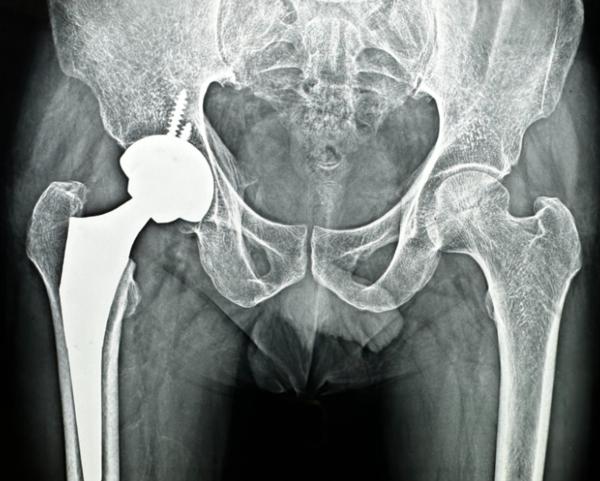

If joint pain is slowing you down, finding the right surgeon makes all the difference. At Phoenix Orthopedic Superspecialty Hospital in Nagpur, we offer expert care from some of the best joint replacement surgeons in the region. Whether you're dealing with arthritis, fractures, or degenerative conditions, our orthopedic team is here to guide you through every step of the recovery process.

Using the latest techniques and personalized approaches, our specialists perform safe, precise surgeries with minimal downtime. We ensure that each patient is well-informed and supported throughout their treatment journey.